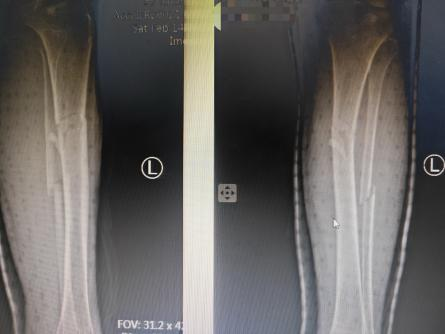

接诊的杜龙龙主治医师第一时间为老人完成详细查体、病史采集,结合影像学检查,快速明确“左小腿胫腓骨骨折”的诊断。杜龙龙医师深知,手术治疗已无可能,中医手法复位成为唯一可行方案;但老人高龄骨骼脆性大、软组织条件差,且有基础疾病,复位操作容不得半点差错。他当即向科主任董博主任医师、副主任医师周健详细汇报病情,三位专家迅速展开联合诊疗。

复位后复查X线片显示,老人骨折断端对位对线良好,患者疼痛感也明显缓解。看到治疗效果,家属悬着的心终于落地,对团队连连道谢,对治疗效果表示高度认可。